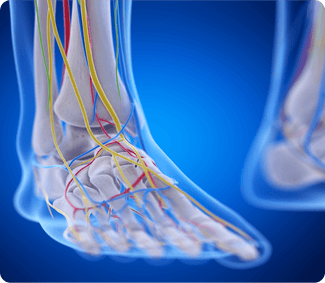

Neuropathy can be painful and persistent but you can find relief. Most people don't realize neuropathy pain can be influenced by poor circulation in the foot. Poor circulation is often the result of improper alignment of the ankle. By correcting ankle alignment, Protalus insoles increase circulation and bring you noticeable relief from your neuropathy pain.

Protalus puts your ankle in a natural position, properly distributing pressure, increasing circulation and providing the best circumstances for nerve health.

Nerves require a constant supply of oxygen and nutrients to function properly. Poor circulation limits the delivery of oxygen and essential nutrients to nerve cells, leading to oxidative stress and damage.